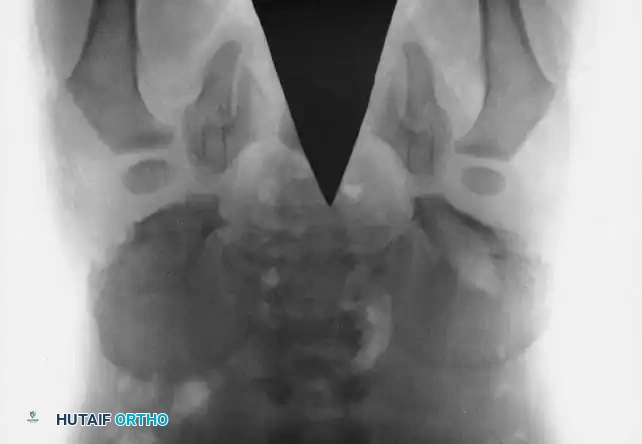

Fig. 27-38 B: Postoperative anteroposterior radiograph demonstrating successful closure of the pubic diastasis following bilateral anterior Salter innominate osteotomies and application of an external fixator.